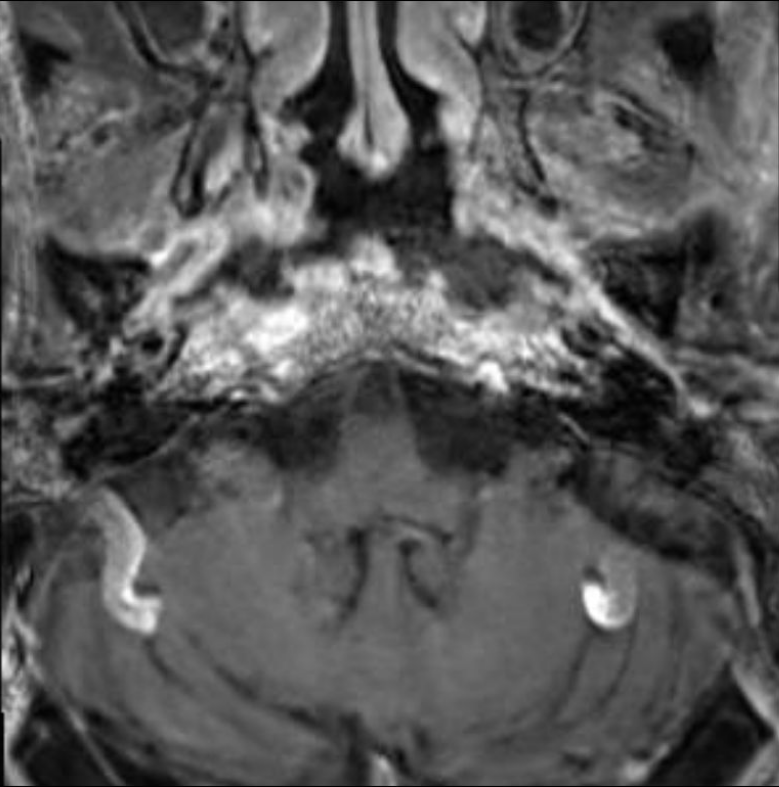

MRI检查:全组鼻窦炎,双侧咽鼓管区、咽旁间隙、斜坡区域异常信号,不均匀强化,双侧乳突炎